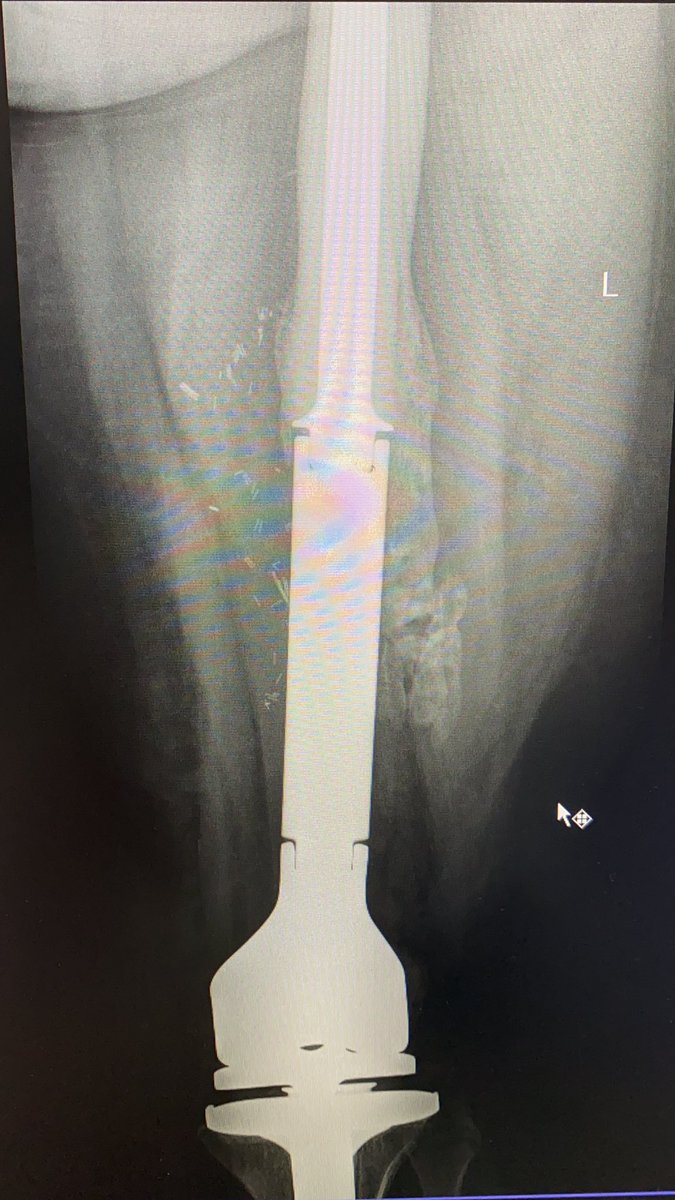

عادة تعالج الساركوما بالكيماوي او الاشعاعي و اهم خطة في العلاج هي الجراحة لاستئصال كامل الورم. هذا النوع من العمليات معقدة و طويلة جدا و تحتاج احيانا الى جراحين من اكثر من تخصص. عادة ما يتم استءصال العظم مع الورم و يصبح فراغ عظمي كبير يستدعي استبدال العظم و المفصل معا او العظم...

...فقط اذا كان بعيد عن المفصل. لا افهم لماذا يوافق التامين على استئصال الورم و يرفض عملية استبدال العظم و المفصل رغم ان العملية هدفها انقاذ حياة المريض من السرطان. هل يعقل ان يزال الورم و يترك مكانه فارغ. هذه ليست عمليات استبدال المفاصل العادية التي تجرى لخشونة المفاصل